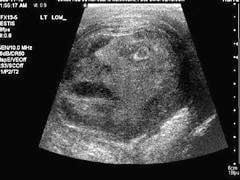

Une radiographie d'un testicule représentant un visage humain hurlant de douleur!

Il est vrai que l'image a de quoi interroger quand on sait que le patient s'est rendu à l'hôpital parce qu'il souffrait terriblement au niveau des testicules. Après avoir constaté la présence d'une tumeur, les médecins ont décidé de pratiquer une échographie et ont été stupéfaits de son résultat.

La tumeur, qui s'est révélée bénigne, a pu être retirée sans dommage et l'homme de 45 ans a repris sa vie normale. Sa radiographie, elle, fait le tour du monde.